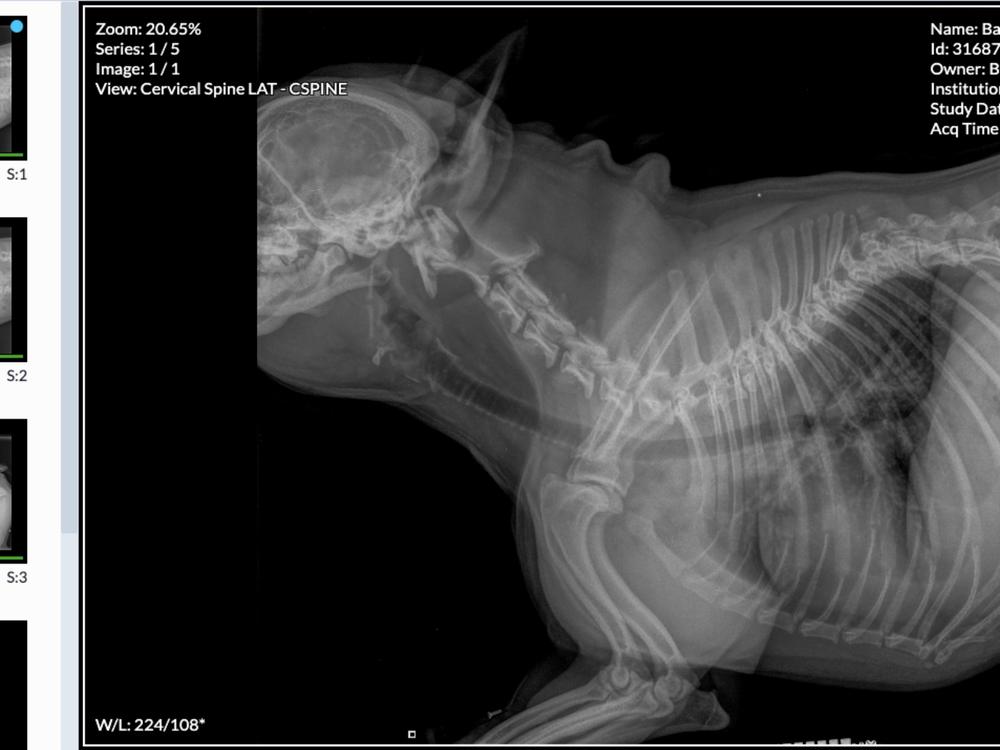

My gorgeous 3 year old French Bulldog, Bardot has a devastating spinal deformity that is pinching her digestive nerve. She is very unwell and needs an MRI and possible surgery if the MRI shows they can do anything. She is my baby as most of you will know. We have spent thousands already trying to get her pain under control and find out what is wrong. On Friday I thought my only option was euthanasia but with your help I believe we can do something for her that will give her a better chance at being assessed by the ARC specialist team in Auckland. I brought her home from the vets on Friday and she has had a very drugged weekend but is comfortable, settled and relatively happy until I can get her further help. She is an amazing wee girl that does not deserve this. I am absolutely devastated, gutted, cut up and this is my one opportunity to be able to help her. Please, those that know me and Bardot will know the pure joy and love she has brought to many children in the classroom daily and love she has shared with friends. She has her favourite people and they have all visited this weekend. No one want a to say goodbye! Let’s give her that chance. Any little bit will help. Thank you, thank you. I will keep you updated. Love Bardot, Kathryn and Melanie

Thank you ALL for your support. Bardot is home again after her assessment and testing at ARC in Auckland. She has a herniated disc in her neck which they initially want to treat with 4 weeks strict crate rest then back to ARC and if no improvement then surgery will be required. Fingers crossed she heals and recovers. Yet again thank you for your support, the money raised to date covers a little of what we have spent, it is hugely appreciated. Love Kathryn, Melanie and Bardot